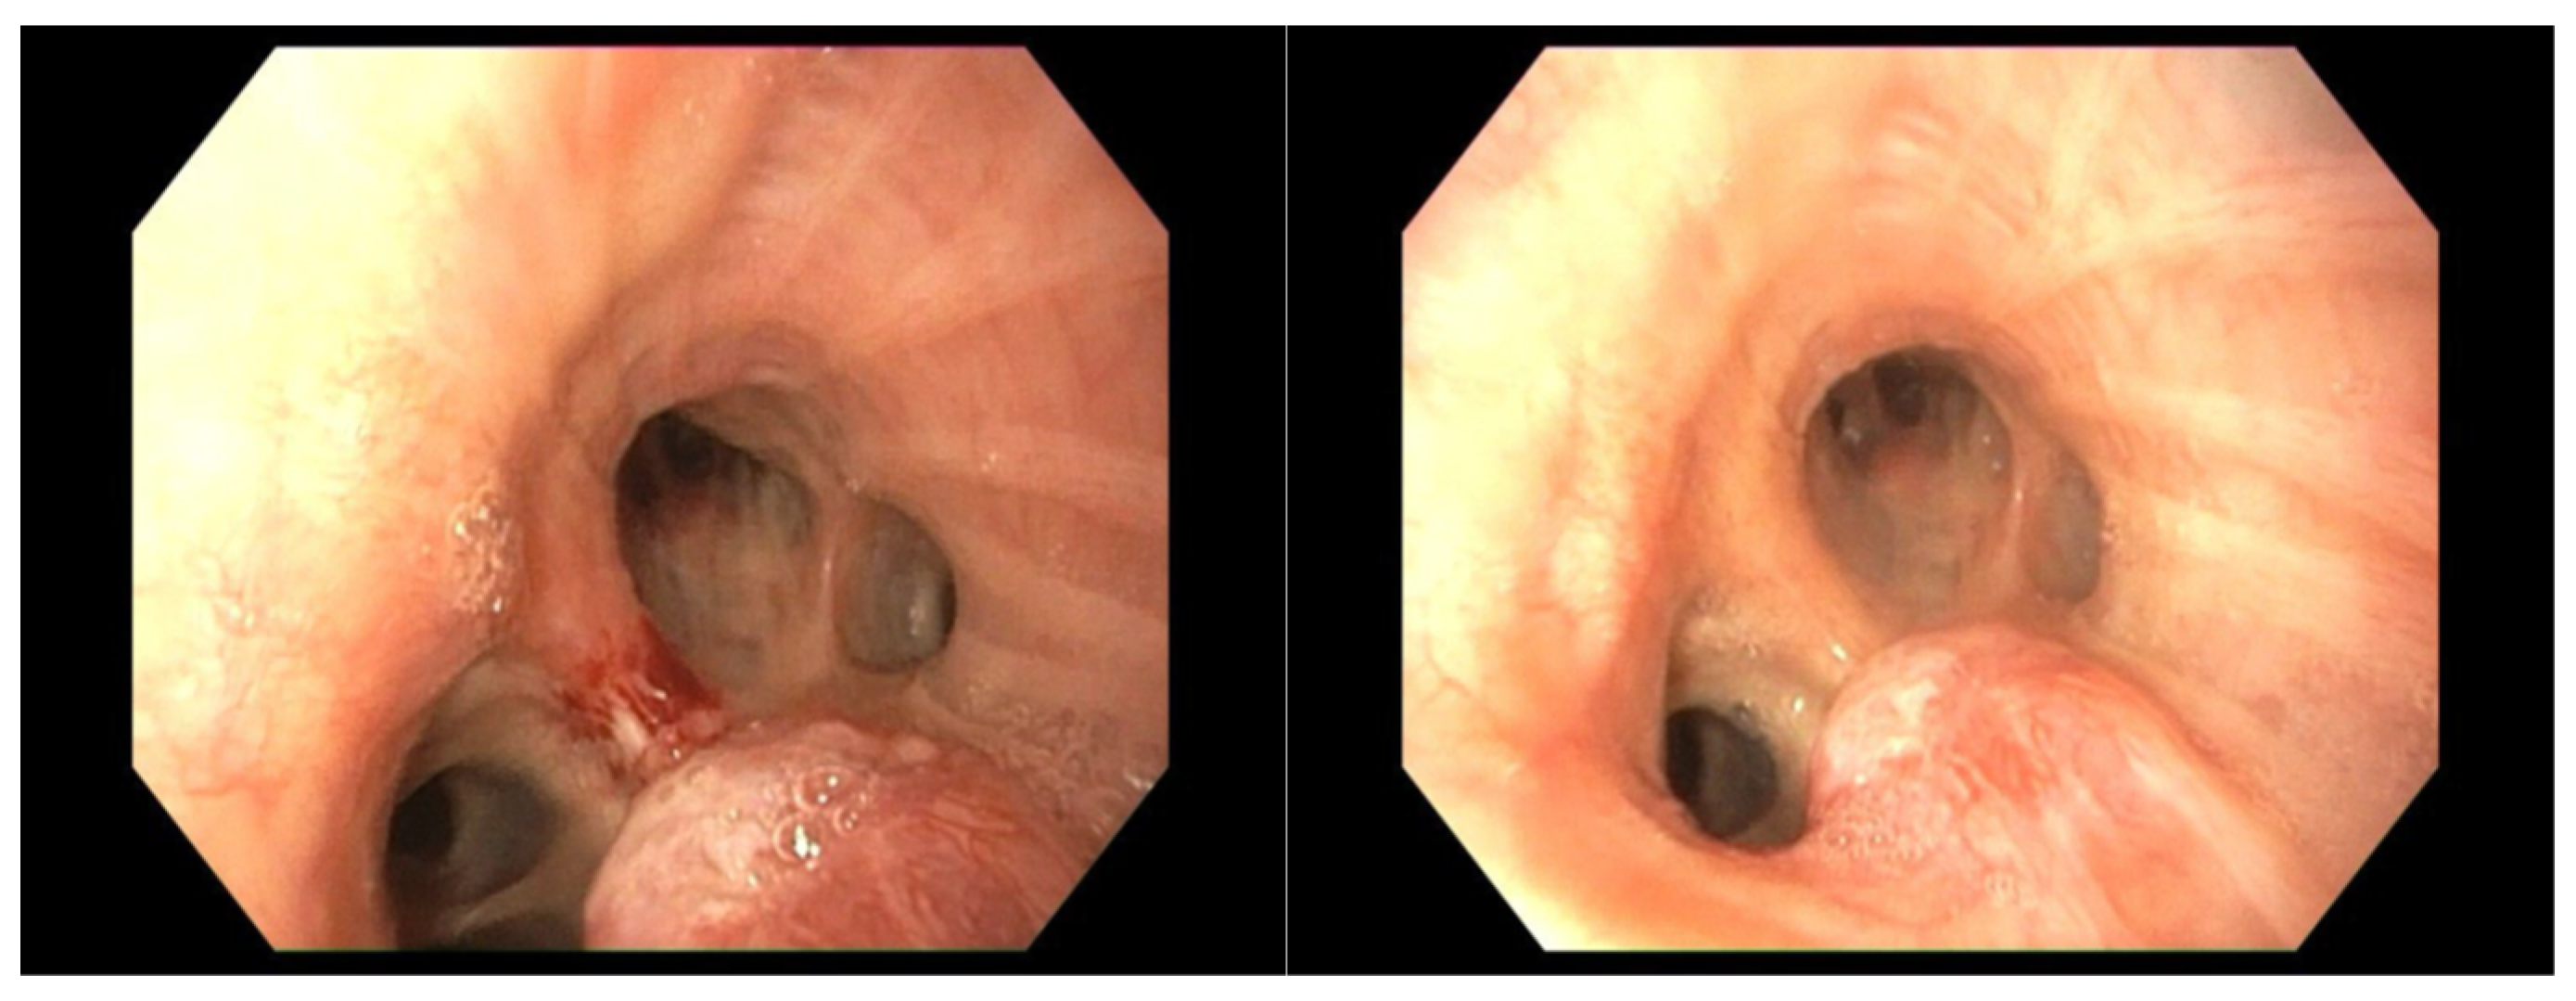

4.2. Case 2